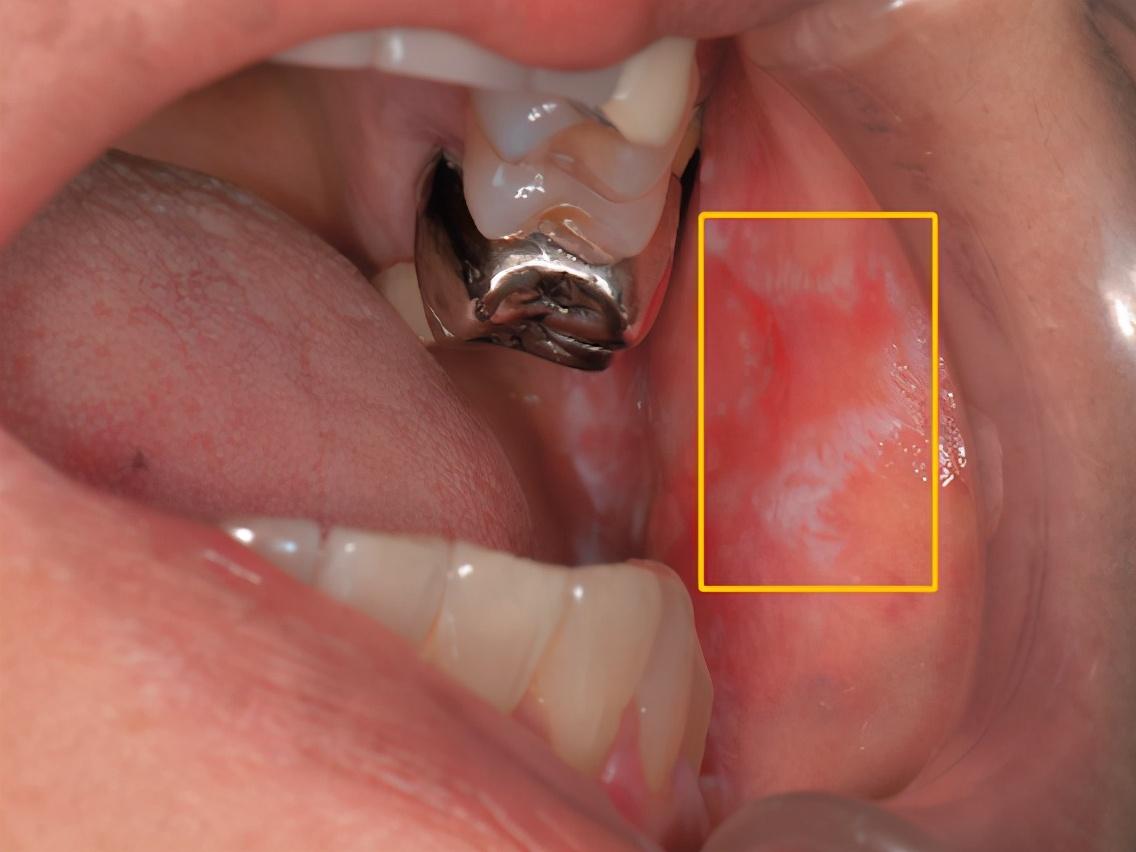

口腔内出现白色条纹,医生怀疑可能癌变?这种令人担忧的情况,实际上可能是口腔白斑病的症状。虽然大多数口腔白斑病并不一定会发展成癌症,但确实存在一定的癌变风险,不容忽视。

口腔白斑病是一种常见的非传染性慢性疾病,主要表现为口腔黏膜上的白色或灰白色角化性病变。这种病变可能呈斑块状、颗粒状、皱纸状或疣状。其中,斑块状是最常见的类型,表现为无法清除的白色或浅灰色斑块,表面可能粗糙、高低不平或光滑。颗粒状白斑则多见于口角区,常伴有红色区域。皱纸状白斑多出现在口底和舌腹,而疣状白斑则表现为隆起的乳头状或毛刺状突起。